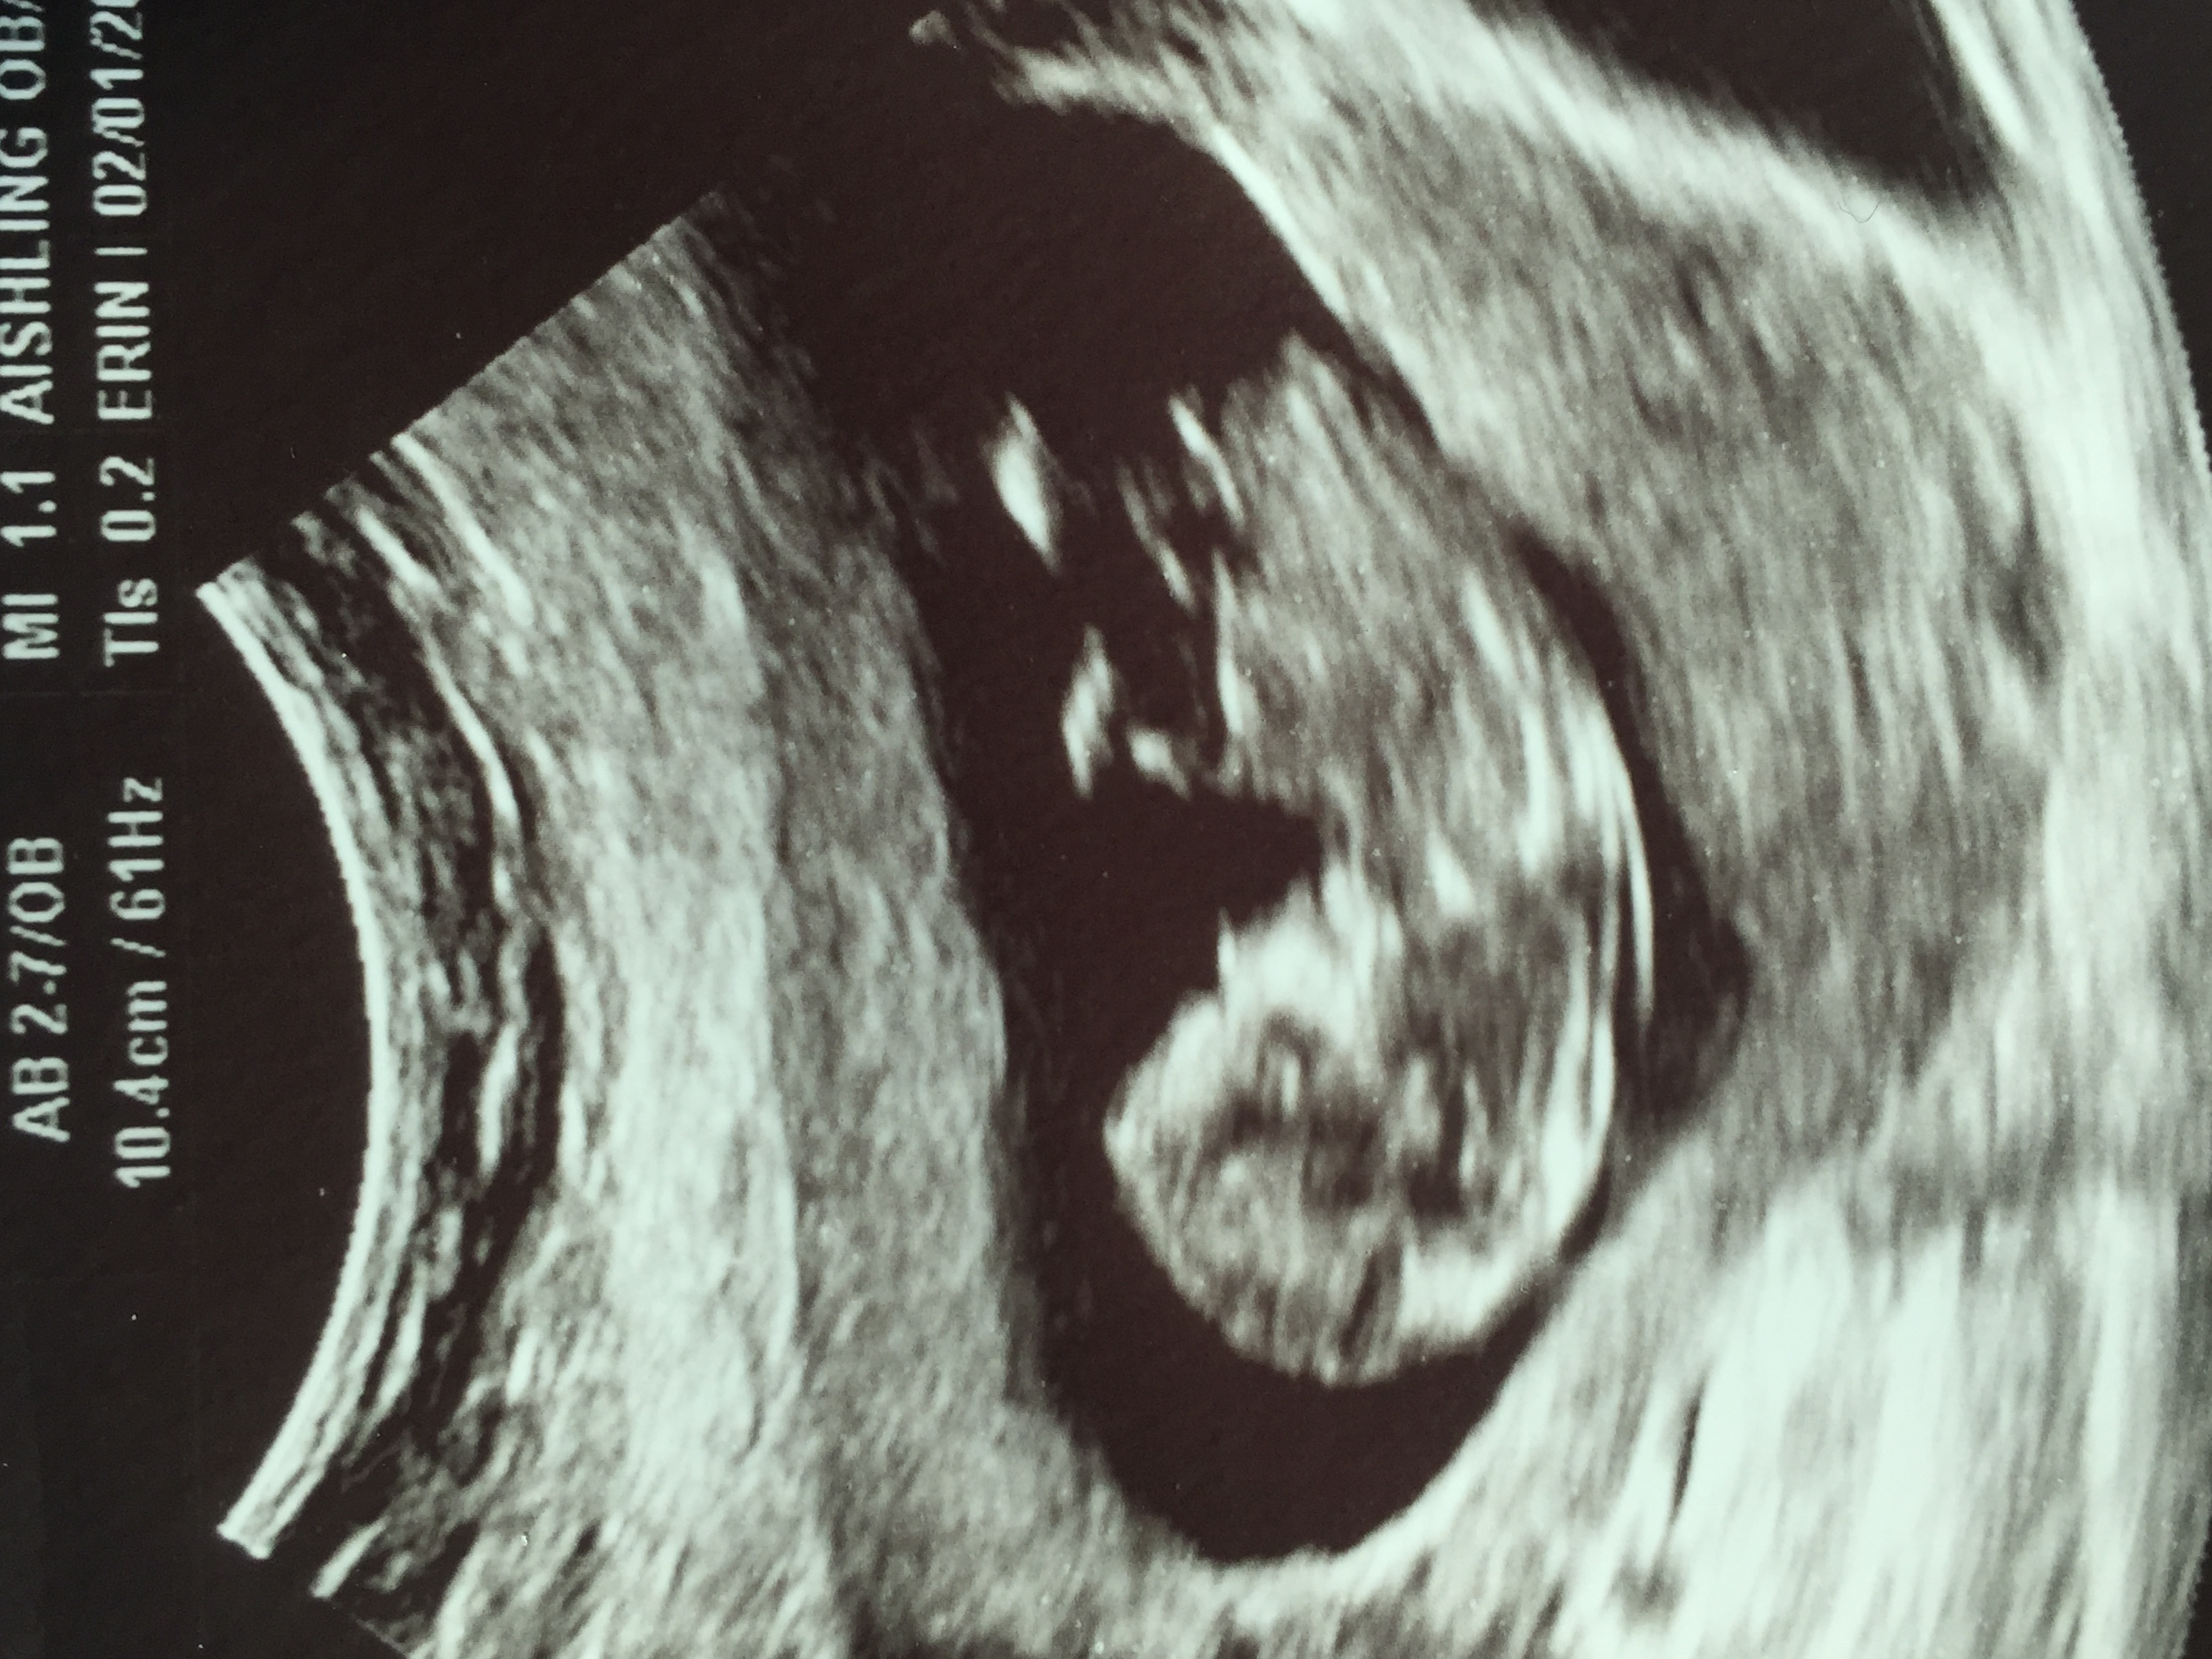

12-5 nub guesses please! 😊